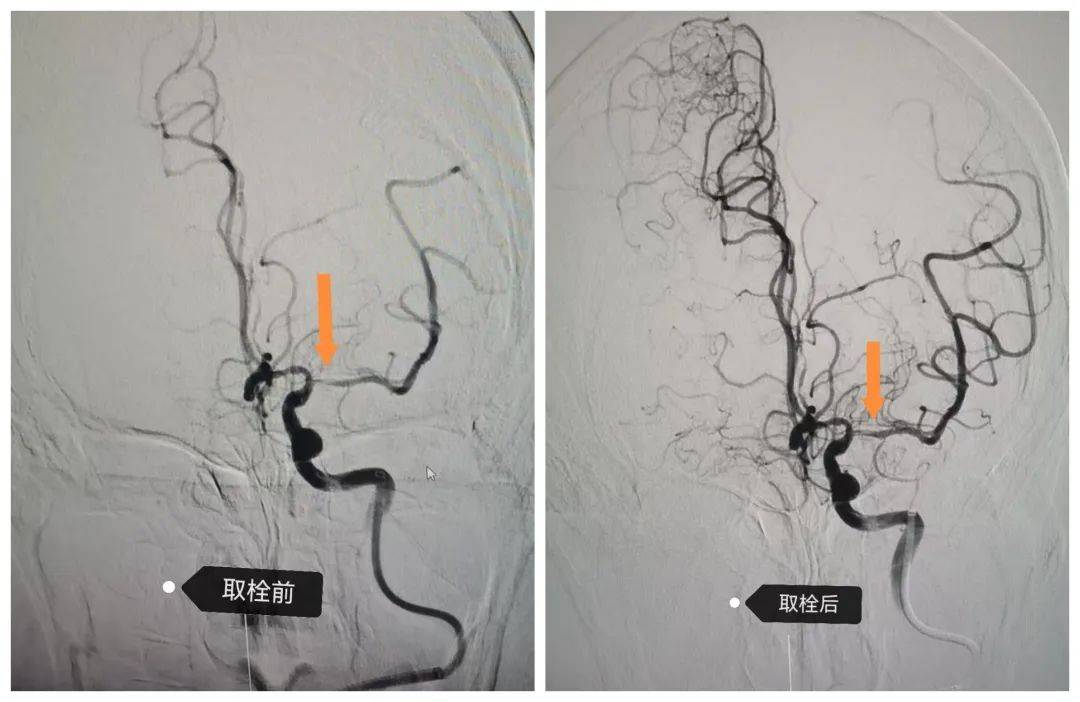

01七十歲老人的“生命堤岸”——溶栓與取栓的無縫接力

70 歲的武大娘晨起突發(fā)右側(cè)肢體無力,急診120送達(dá)殷都區(qū)人民醫(yī)院時(shí)已無法行走。神經(jīng)內(nèi)科綠色通道醫(yī)師張偉艷在39分鐘內(nèi)完成評估,確診急性腦梗死并啟動靜脈溶栓治療。然而,溶栓后15分鐘患者癥狀加重,出現(xiàn)意識障礙。介入醫(yī)師梁麗平、張曉亭緊急評估后,決定實(shí)施急診取栓術(shù)。在癥狀加重 1小時(shí)后,手術(shù)團(tuán)隊(duì)于全麻下成功完成顱內(nèi)取栓。10余天后,武大娘在家人陪同下康復(fù)出院,重新回歸平靜生活。